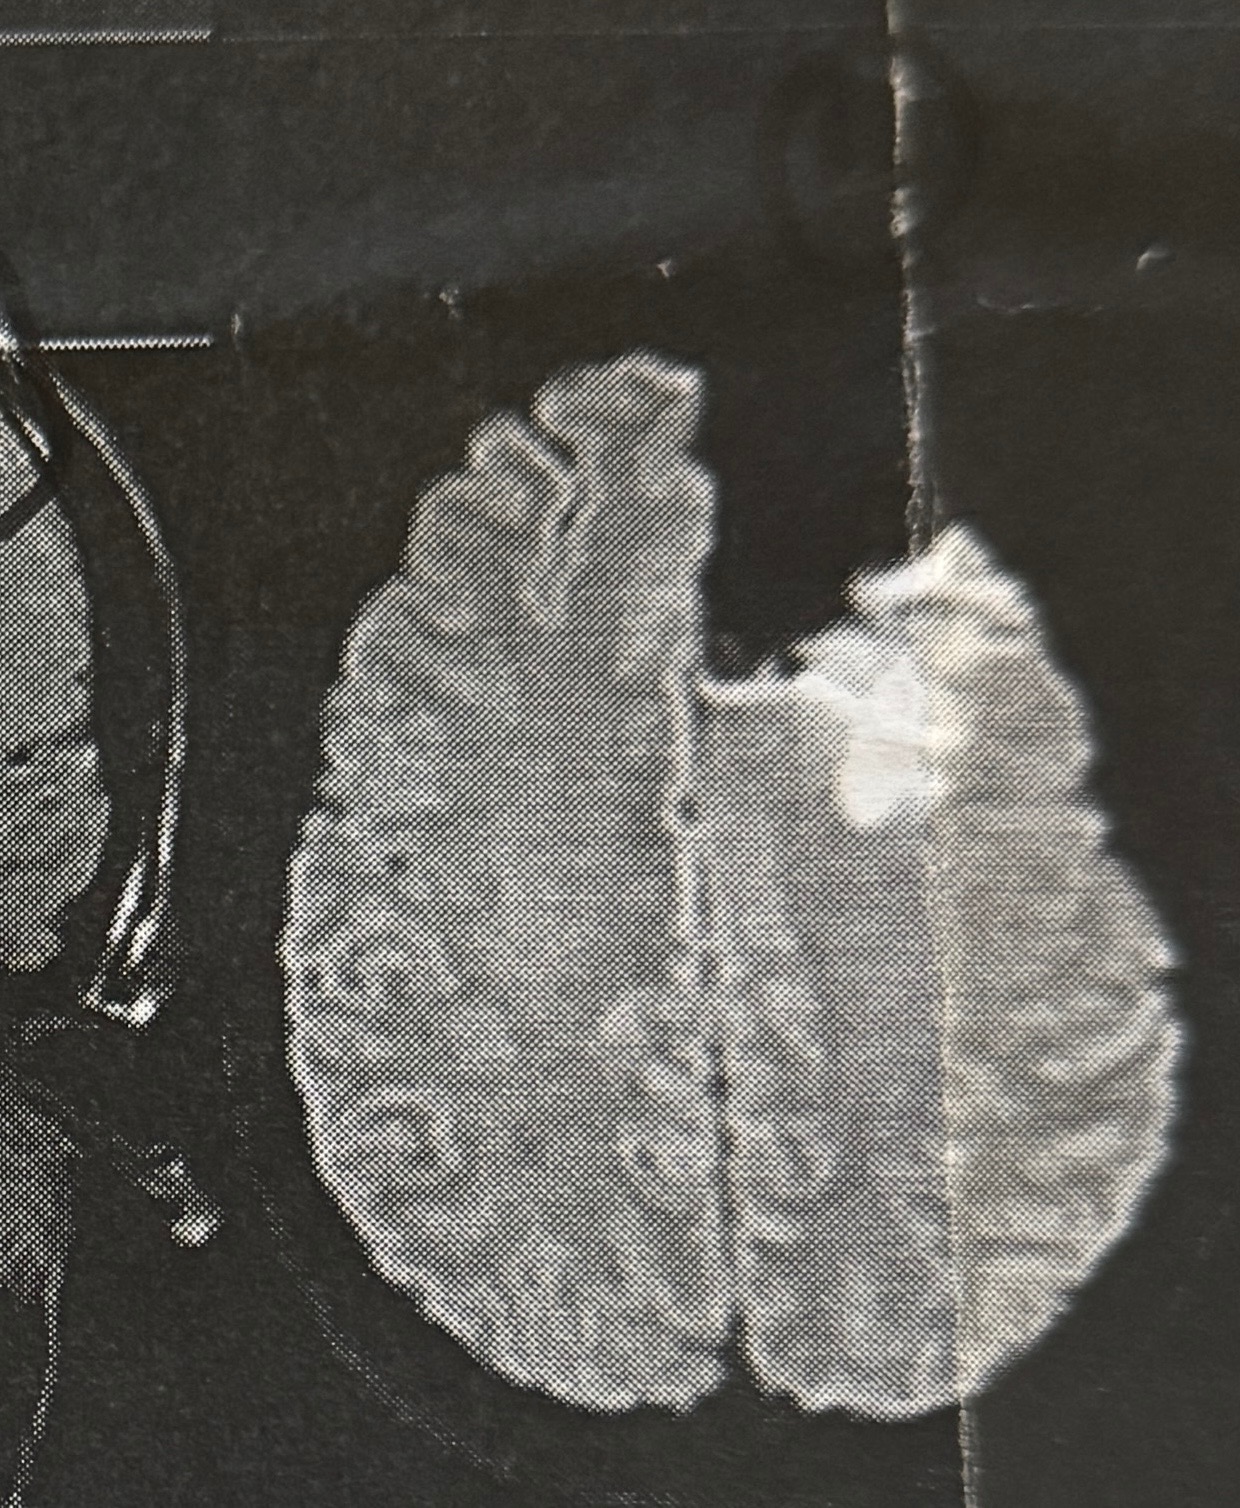

Back in August, I was diagnosed with a Grade 3 Astrocytoma brain tumor in my left frontal lobe. I had a craniotomy, which was performed by an amazing neurosurgeon, Dr. Mohamad Khaled, at Hartford Hospital. They were able to remove about 80% of the mass, and we are actively treating it with chemotherapy and radiation (which I am 3 weeks into of 6)